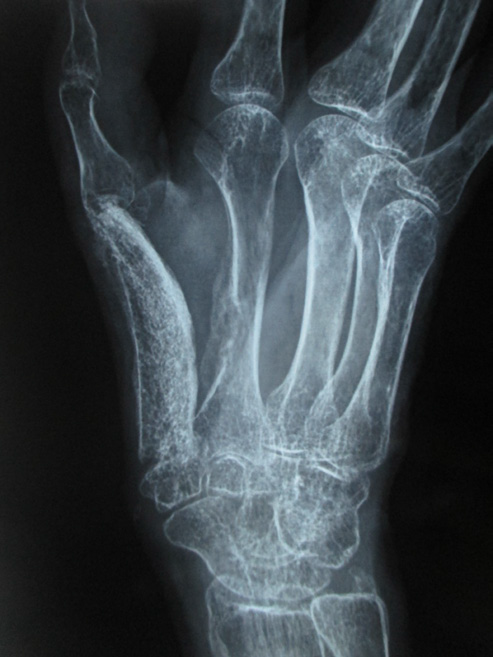

In November 2015 one 60 years lady presented in a newly recognised Medical College of eastern India (Murshidabad Medical College) with recurrence of GCT of the 1st MC of left hand and soft tissue involvement. One year back she was presented in another medical college with intraosseous Capancci grade III lesion of the same site of two years duration where it was treated with narrow margin resection, interposition bone cement on a Kirschner wire (K wire) (Figure 1). It started recurring after 8 months of resection. But presented to us after another one year when extensive extension within soft tissue took place. In plain x ray one small osteolytic lesion was noticed over mid shaft of second metacarpal of the same hand which was not seen in earlier radiographs. MRI was done to identify adjacent bone involvement and to know extent of the lesion in soft tissue (Figure 2). Involvement of regional lymph node and lung metastasis were excluded clinically and radiologically.

Figure 1 a. Initial X-ray initial presentation 3 years back; post-operative X-ray after initial operation; b. immediate; c. subsequent.

Under tourniquet control and regional anaesthesia through dorsoradial incision the mass along with bone cement was removed, meticulously cleaning of original tumour site was done. Excised tissue was preserve for histopathology (HP). With a separate set of clean instrument the osteolytic area second metacarpal was curetted and the material is preserved in separate jar for HP study. Tricortical bone graft from iliac crest of appropriate size was harvested and placed in position with 4 K-wires. After closure of wound hand and forearm was placed in plaster of Paris slab. Stitches were removed after 2 weeks but cast continued for 2 months and K wires continued for 3 months when graft ends started uniting and partially incorporated (Figure 3). Histopathology reported as GCT without malignancy from both the specimens. 75 % movements of carpometacarpal and metacarpo-phalangeal joints were restricted but interphalangeal joint exhibit 50% motion (Figure 4). Wrist became free. In 1 year 3 months follow up there is no evidence of recurrence or metastasis. Considerable amount of reactive consolidating bone formation around 2nd MC radiologically.